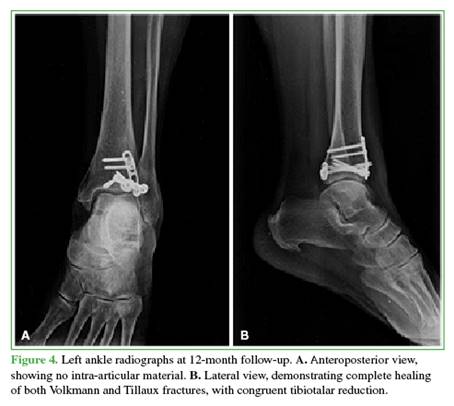

After 12 months, fracture healing was confirmed (Figures 4 and 5), and the patient resumed her usual activities. Her American Orthopedic Foot and Ankle Society (AOFAS) score was 91, and her Olerud-Molander functional scale score was 95 (Figure 6).

Thus, we present our case as a rare bimalleolar equivalent fracture: Volkmann and Tillaux in an adult, with no other associated injuries. This represents the eighth reported case in the literature over the past six decades. Reduction and fixation of both bony components were performed, successfully restoring the stability of the distal tibio-fibular ring. The patient demonstrated favorable clinical and radiological evolution, achieving functional recovery and complete fracture healing.